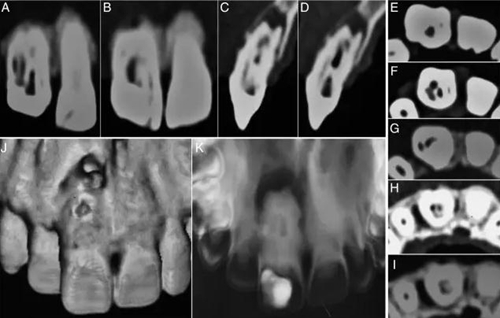

在討論完治療風險和成本等相關事項后患者簽署了知情同意書。橡皮障隔離,局部麻醉下開放髓腔,去除齲壞和腐爛的牙體組織。在清洗完冠部通道后用牙髓探針DG16來定位根管口。逐漸去除牙膠的同時用3%次氯酸鈉沖洗(圖1C)。隨后在釉牙骨質(zhì)界附近發(fā)現(xiàn)了兩個主要根管開口,并用手用擴孔挫2、3和4擴大。用10#和15#k銼探索直到遇到阻礙。用17%EDTA和3%次氯酸鈉沖洗。在初步?jīng)_洗和暫封后,病人拍攝了CBCT,顯現(xiàn)了牙體內(nèi)部形態(tài)的3維結(jié)構(gòu)(2A–K)。復診在牙科顯微鏡下探查根管,發(fā)現(xiàn)近中根管口通向一個寬的Oehlers III型b的牙內(nèi)陷(MI)。遠中根管口通向2個根管,近遠中根管(DM)根管和遠中根管,還有一個在最遠中部分的盲袋。盲袋是Oehlers II型的第二類牙內(nèi)陷(DI),因為它終止在根中1/3。此外,還發(fā)現(xiàn)了近中切角處一個近中根管(M) (圖3A and B)。一共發(fā)現(xiàn)了5個根管并且他們之間互有交通。所有的根管除了DI都終止于一個大口徑的根尖孔。因此,牙齒被診斷為雙重牙內(nèi)陷,包含Oehlers III型b和II型。牙髓根尖周病變被診斷為慢性根尖膿腫。

圖3:A:5個根管開口;B:DM根管傾斜走形,在MI頰側(cè);C和D:倒充填和MTA使用后的圖像。

兩周后患者無不適,進行根管充填。由于根管間有很多的交通(5A),所以在治療過程中15#K銼陷入M和MI間的交通支中并和柄分離(5B)。使用超聲將分離器械取出后進行徹底蕩洗,干燥后用熱牙膠充填系統(tǒng)進行充填(5C)。一個月后,患者完全無癥狀,復合樹脂充填。在3,6,12月進行了復查(5D)。

圖5:A:根管間有很多相互交通;B:進入MI根管后分離的15號K挫;C:充填后的圖像;D:1年后的隨訪。